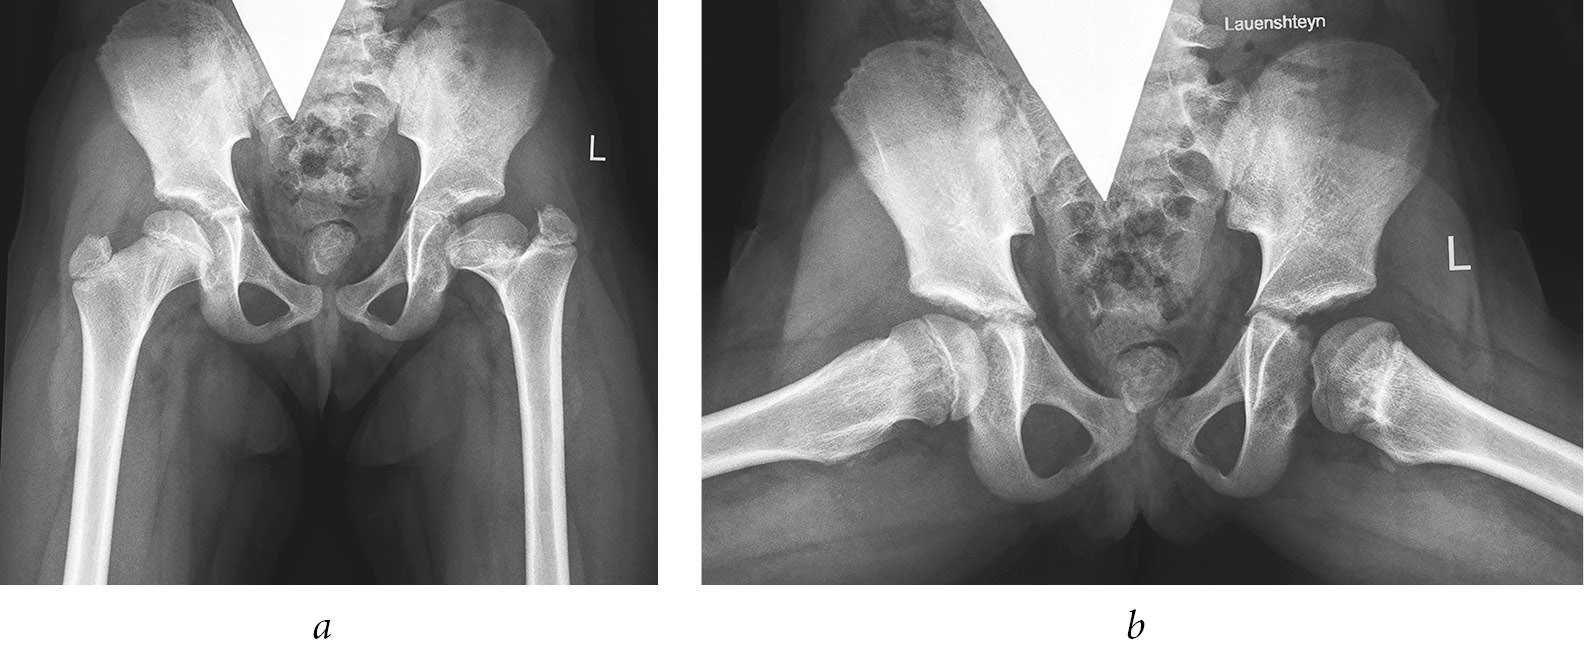

- effects of hematogenous osteomyelitis (septic arthritis) in 101 (28.9%) of all patients. These 101 patients included those who had been exposed to intrauterine infections and those who underwent surgical interventions in the first year of life for congenital heart defects, esophageal atresia, intestinal obstruction, and tracheoesophageal fistula, all complicated by infection of the hip joints (Fig. 4);

Fig. 4. Radiographs of patient J. at the age of 7 years: frontal view (a) and Lauenstein view (b). Hematogenous osteomyelitis resulted in multiplanar deformity of the proximal femur with a high position of the greater trochanter on the left